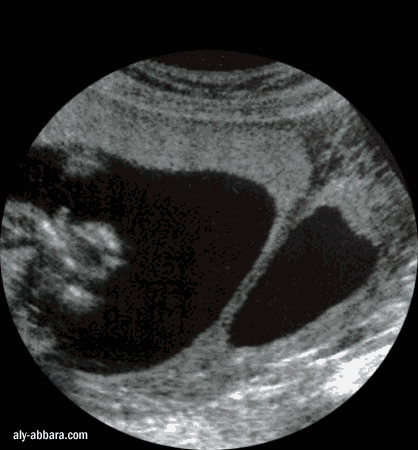

Aspect de l'utérus malformé cloisonné corporéal

chez une femme enceinte de 20 SA

Cloison utérine limitée au fond utérin